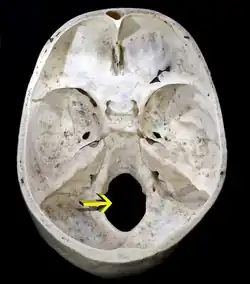

Foramen magnum

Das Foramen magnum (lateinisch für „großes Loch“) oder großes Hinterhauptsloch (Synonym: Foramen occipitale magnum) ist die größte Öffnung des Schädels an der Schädelbasis und wird vom Hinterhauptbein gebildet. Sein vorderer Mittelpunkt wird als Basion, sein hinterer als Opisthion bezeichnet; sie dienen als anatomische Orientierungspunkte für Schädelvermessungen.[1]

Das Foramen magnum verbindet die Schädelhöhle mit dem Wirbelkanal und ist Durchtrittsstelle für das Zentrale Nervensystem (ZNS): Hier gehen Rückenmark und Gehirn ineinander über. Der an das Rückenmark anschließende Hirnteil ist die Medulla oblongata (,verlängertes Mark‘). Auch die spinalen Wurzeln des XI. Hirnnervs (Nervus accessorius), die Wirbelarterie (Arteria vertebralis) sowie ein venöser Plexus nutzen das Foramen magnum als Durchtrittsöffnung.